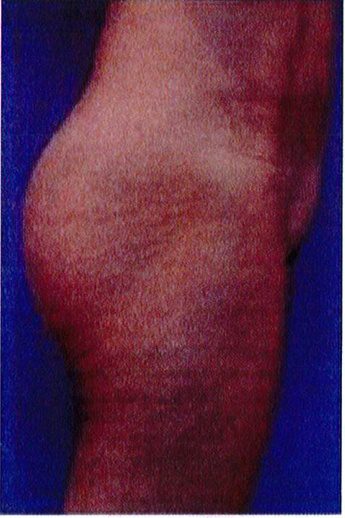

THỜI GIAN HỒI PHỤC SAU MỔ

Bệnh nhân 30 tuổi mong muốn cải thiện hình dáng vòng ba, mặc dù vòng mông đã tương đối đây đặn. Bác sĩ sau khi đánh giá đã đưa ra quyết định hút mỡ eo và làm đầy mông bằng implant. Hai khối implant microtextured (vi nhám) thể tích 330 mL được đặt cân đối ở hai bên. Bệnh nhân sau phẫu thuật xuất hiện bục một phần vết mổ (dài khoảng 2cm) ở hai bên nhưng không sâu và đã điều trị kịp thời bằng dung dịch sát khuẩn, kháng sinh tại chỗ và toàn thân. Vết mổ liền lại tốt (Hình 20).

Hình. 20. (A) Hình anh trước và (B) và sau phẫu thuật làm đầy mông của bệnh nhân có vùng mông tương đối đầy đặn. Bệnh nhân được đặt khối implant dưới cân thể tích 330 mL ở hai bên.